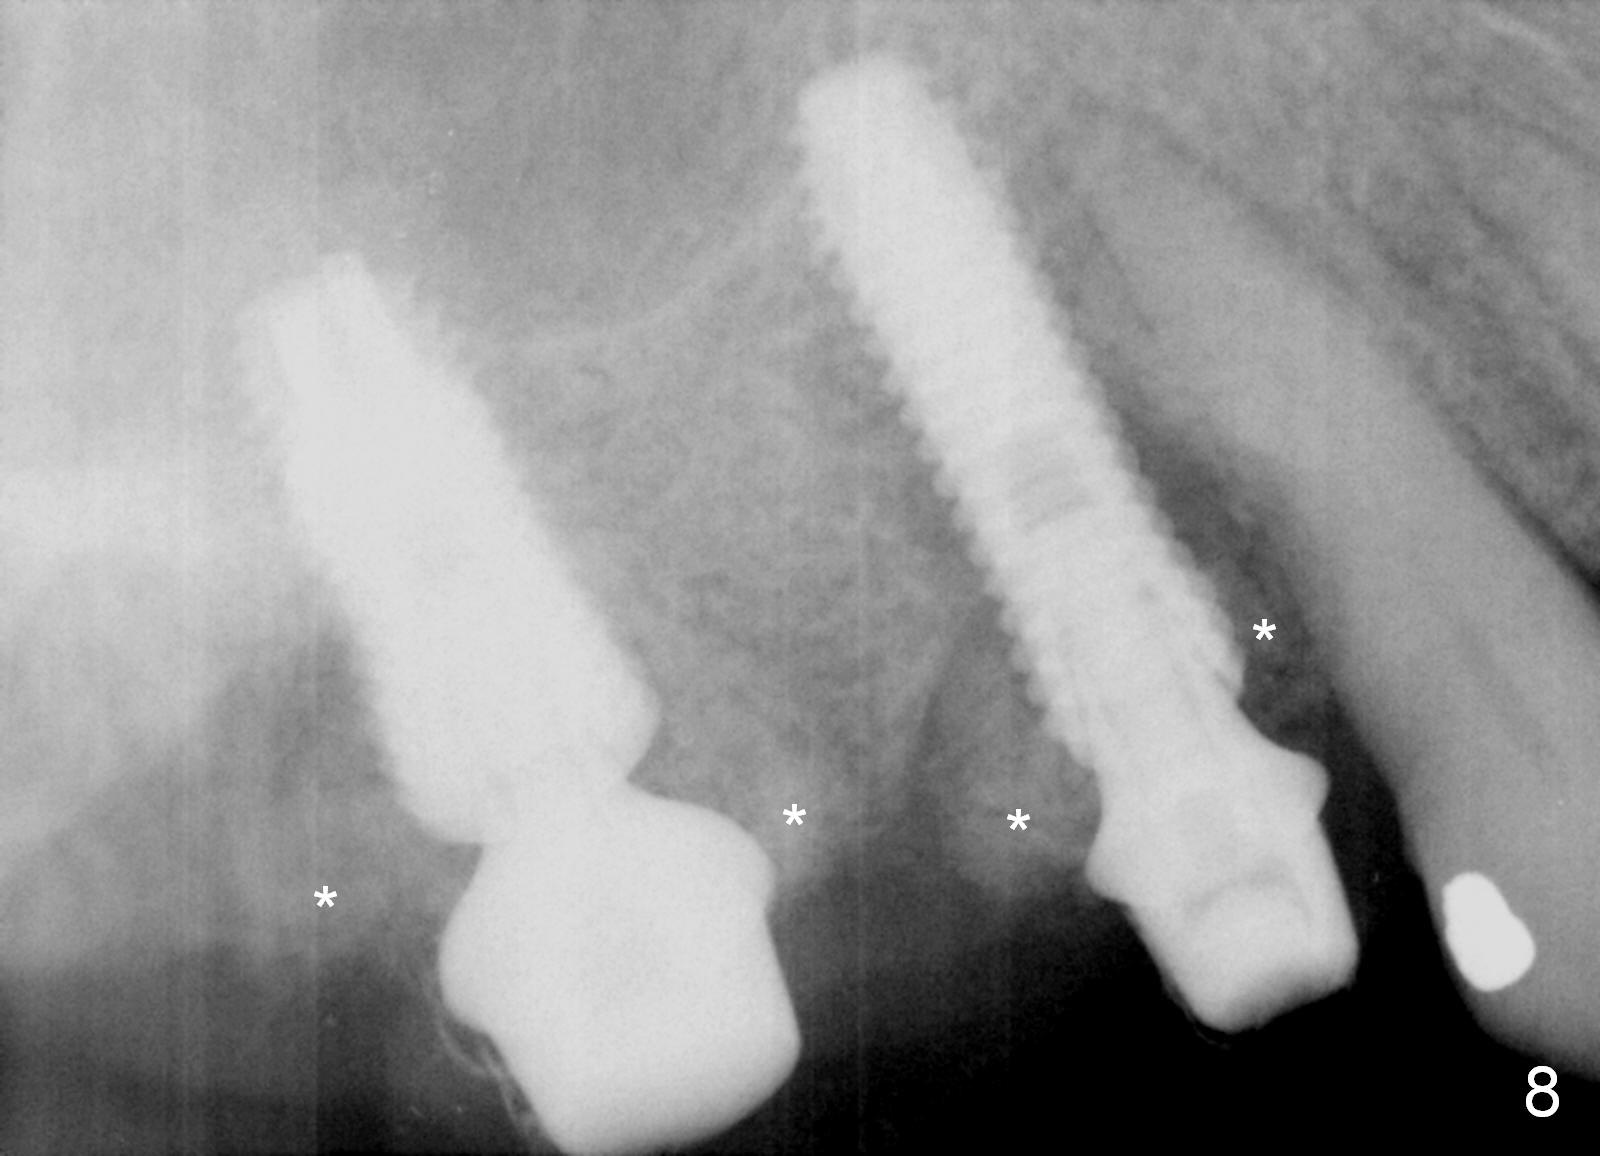

Preop photos show generalized gingival hyperplasia (hypertension med (Amlodipine, Calcium Channel Blocker), Fig.1 *), palatal (Fig.2<) and buccal (Fig.3 B) abscesses originated from the tooth #5. There is a smaller abscess buccal to the tooth #3 (not shown). After extraction, the buccal and palatal plates of the teeth #3 and 5 are found basically non-existent. When taps are placed, large socket defects are evident (Fig.4 *). In addition to sinus lift at #3 (Fig.5 black *), mineralized cancellous and cortical allograft (.5-1 and 1-2 mm) is placed around the implants with healing screws in place (white *). After the healing screws are removed and cemented abutments are placed, more allograft is packed (Fig.6-8 *). Closing the "dead" space in step may prevent immediately postop infection and peri-implantitis.

There is no infection around the implants 1 months postop (Fig.9,10). In fact infection mesial to #6 is more severe than preop (Fig.9 arrowhead, Fig.11). When the provisionals are removed for trimming, there is yellowish bone graft around the abutments, which is apparently not incorporated by the body (Fig.9,10 *). It is easily removed by spraying water. The margin of the abutment at #5 is subgingival; an abutment with a longer cuff should be changed next visit.

Two months and a half postop (#3,5 implantation), the patient agrees to have #6-8 to be extracted because of persistent infection. She reports dislodgement of the provisional at #3-5 using water pik. The provisional is found to be mobile. PA shows decrease in bone density around the implant at #5, probably due to proximity to the infection (Fig.14 *).